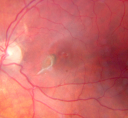

Multifocal Choroiditis and Subretinal Fibrosis - 32 yo Female Macula OS 2 months post rx1027 views32-year-old woman vision loss in the right eye associated with macular scarring and multifocal choroiditis in 1999 with new vision loss in left eye: OD 20/400, OS 20/50.

2 months post-rx with posterior subtenons kenalog and intravitreal avastin - va os 20/30 and lesion has retracted and organized. It never subsequently grew over 2 years follow-up